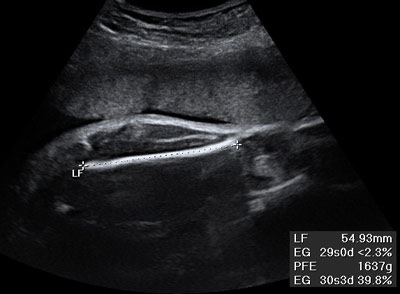

De rutina se mide el diámetro biparietal (medida entre los dos huesos parietales del cráneo), la circunferencia del abdomen fetal y la longitud del fémur.

Es posible hacer una estimación aproximada de su peso. Para ello existen diferentes fórmulas, las más habituales tienen en cuenta la medida del diámetro biparietal (DBP), la circunferencia del abdomen (CA) y la longitud del fémur (LF). Se trata por tanto de una estimación. El margen de error puede llegar a ser de más menos del 15 al 20 por ciento. El peso estimado se compara con tablas de referencia que nos dan el percentil o la desviación estándar sobre el peso teórico.

En términos generales, un feto pesa 1.000 gramos en la semana 28, 2.000 gramos en la 32, y 2.500 gramos la semana 35. Suele aumentar 200-250 gramos semanales desde la semana 28 hasta la 38.